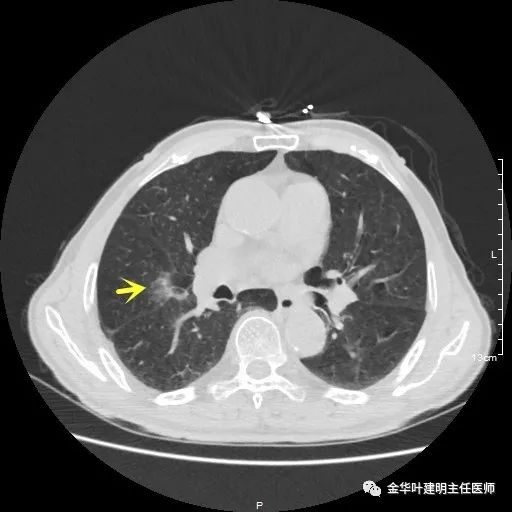

以上示右下叶病灶5。也是主病灶,是实性块状分叶的占位性病变,基本可以肯定是肺癌。单病灶看需下叶切除并清扫淋巴结。